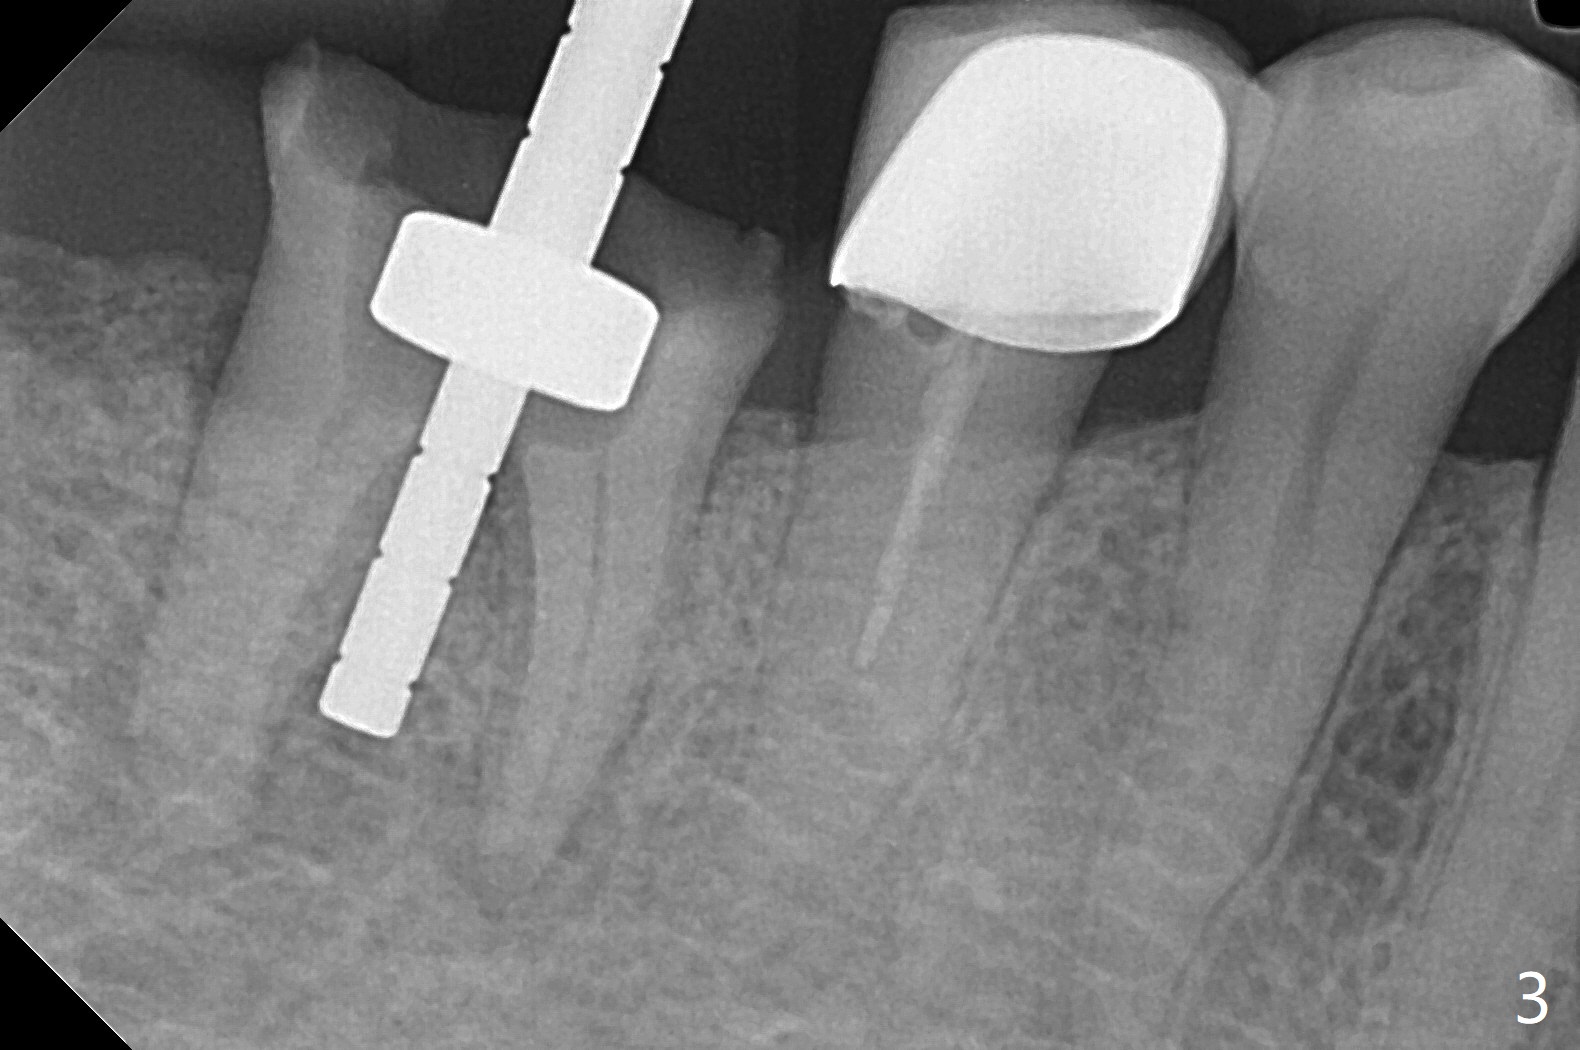

A 59-year-old woman with severe pain and mobility at #30 returns to clinic for extraction and implant on emergency basis (Fig.1 ^: crazing line). To prevent osteotomy deviation off the septum, the crown is sectioned (Fig.2) and the coronal end of the septum is exposed. In fact the initial osteotomy is blind (Fig.3). After increasing the access (Fig.4), trying to change trajectory and increasing the depth and diameter of the osteotomy, the trajectory deviates to the distal socket (Fig.5). Following root extraction, debridement of the sockets and minor trajectory change, a 4x11 mm dummy implant is placed (Fig.6). With a drastic change in osteotomy, the dummy implant position is somewhat acceptable with a 5.2x4 mm planning abutment (Fig.7 P). After placement of bone graft around the 4.5x11 mm final implant to enhance stability, a 5.5x4(3) mm definitive abutment is placed in a restorable position (Fig.8). The implant turns while the abutment screw is hand tightened. Since there is an apical space (Fig.8 <), the implant is then placed ~ 1mm deeper with ~ 30 Ncm (Fig.9). A longer cuffed abutment is inserted and more bone graft is placed (*). In summary, roots in the sockets do not seem to help free hand osteotomy in the lower 1st molar. It is also difficult to control pain during acute infection. Block anesthesia has to be administered, increasing the chance of nerve injury. Either guided surgery or delayed implant should be conducted. There is no postop paresthesia, although the buccal gingiva is slightly erythematou, edematous and tender 1 week posotp. Oral Amoxicillin is prescribed for one more week. The keratinized gingiva (Fig.10 ^) and the papilla (*) are maintained in place around the immediate provisional (P) 2 months 20 days postop. The soft tissue remains normal 4 months postop (Fig.11) and immediate pre cementation (Fig.12).